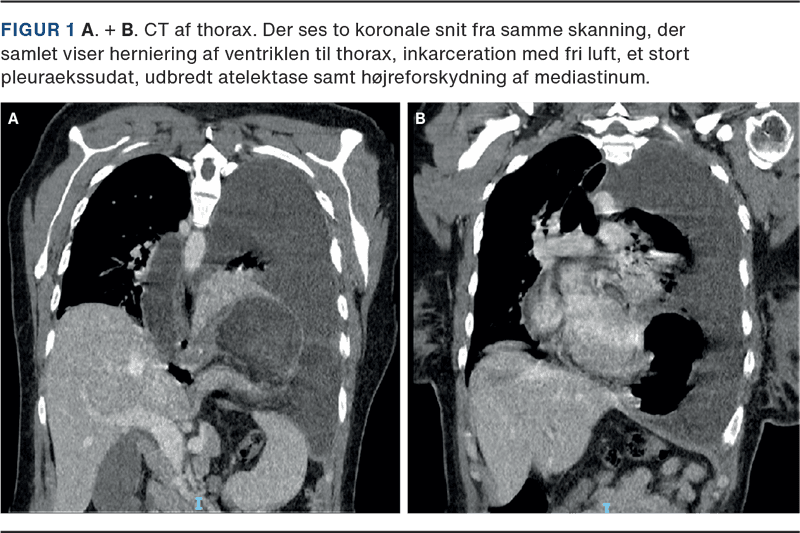

En CT af thorax viste herniering af ventriklen til thorax, inkarceration, stort pleuraekssudat, udbredt atelektase og højreforskydning af mediastinum (Figur 1). Recidivet var hidtil ukendt.